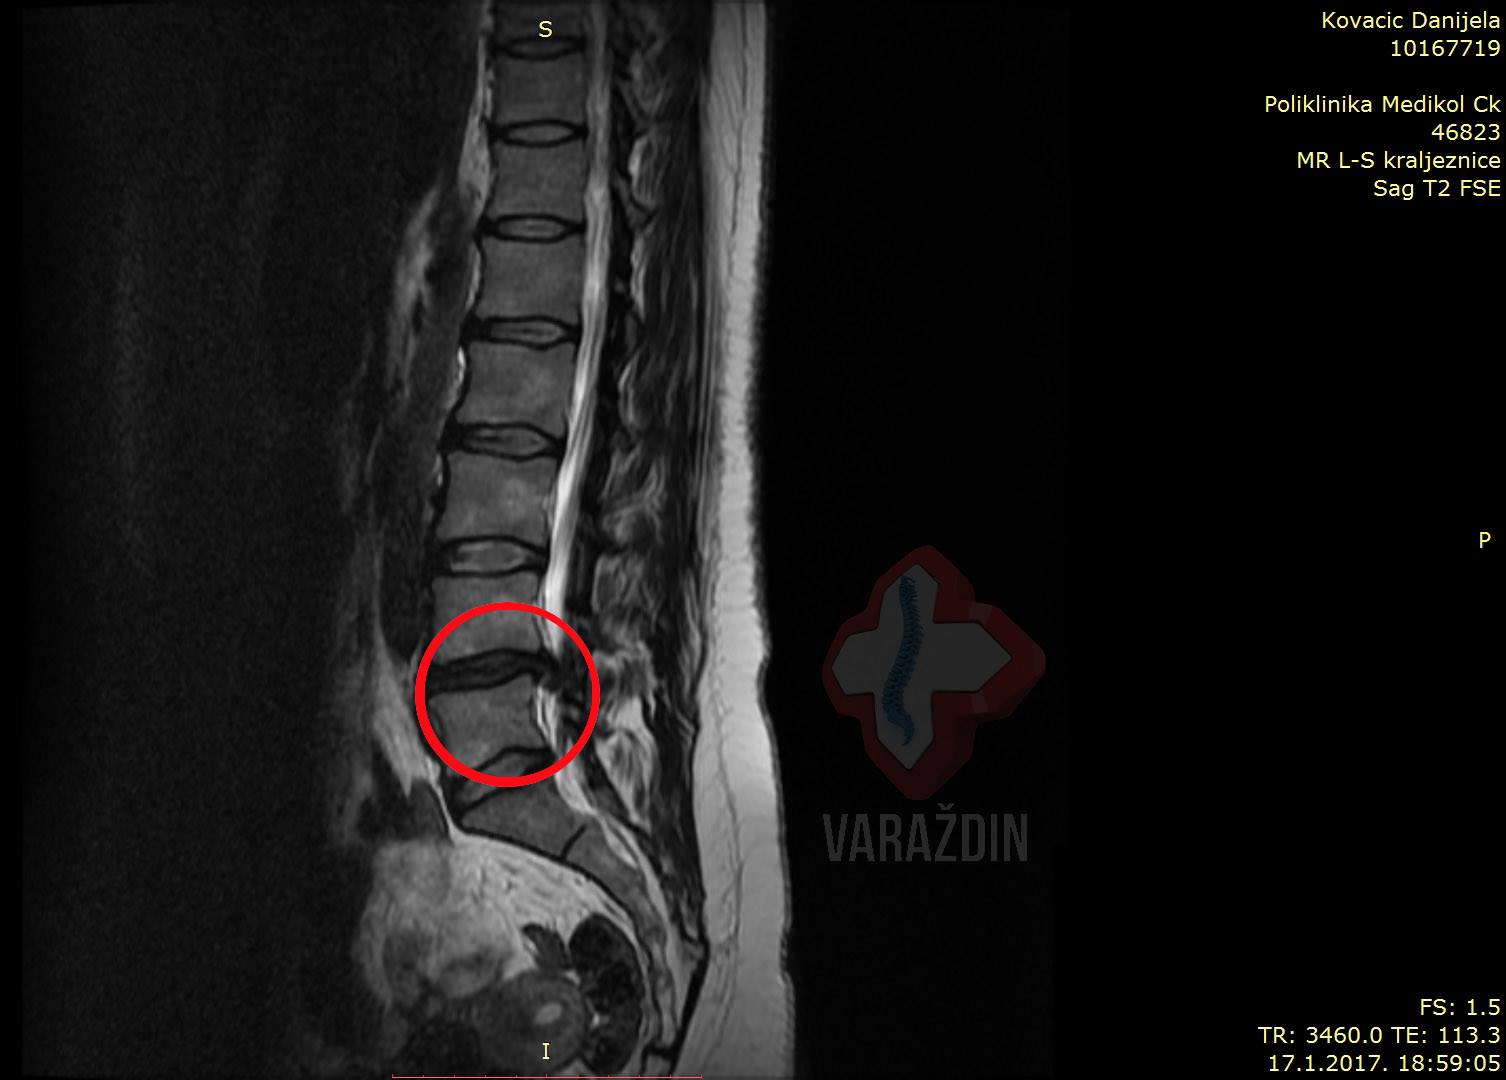

Gospođa Danijela Kovačić prvi puta javila nam se

i posjetila Nado centar zdravlja Varaždin nakon

kiropraktičarskog zahvata nakon kojeg se stanje pogoršalo. Uvidom

u MR snimku uočena je prisutna ekstruzija diska

L4-L5 – dakle – predoperativnog stanja. Od boli

je bila ograničena na ležanje na lijevom boku. Zbog straha od

operacije i nade u potencijalno poboljšanje stanja uspjeli smo

disk dovesti do protruzije zbog čega je došlo do regresivnog

stanja diska između diska L4 i L5. Do potpune

regresija kao što se i vidi na pratećim slikama nije

došlo, ali bol je nestala.